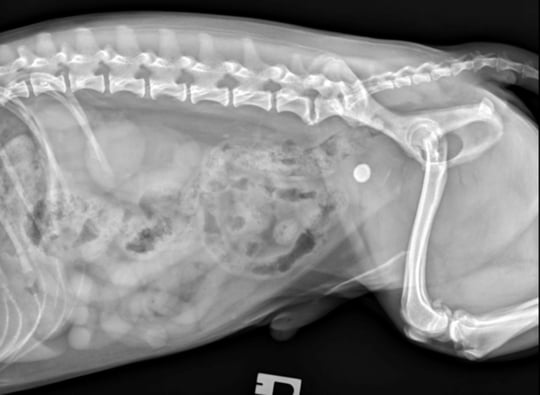

Haematology was also unremarkable, but biochemical analysis and urinalysis confirmed severe renal azotaemia (Figure 1). Abdominal ultrasonography failed to identify an underlying cause for the patient’s profound stranguria, and a contrast enhanced retrograde urethrocystogram was performed. This was unremarkable, and the patient was diagnosed with reflex dyssynergia (Figure 2).

The renal azotaemia and acute kidney injury were thought to be secondary to meloxicam therapy and urethral obstruction. Meloxicam was discontinued, and the patient was hospitalised with intravenous fluid therapy. An indwelling urinary catheter was placed for in-hospital management while tamsulosin and diazepam therapy were started. An immediate response to therapy was noted, and the patient recovered fully. Medical management was discontinued nine weeks after presentation.